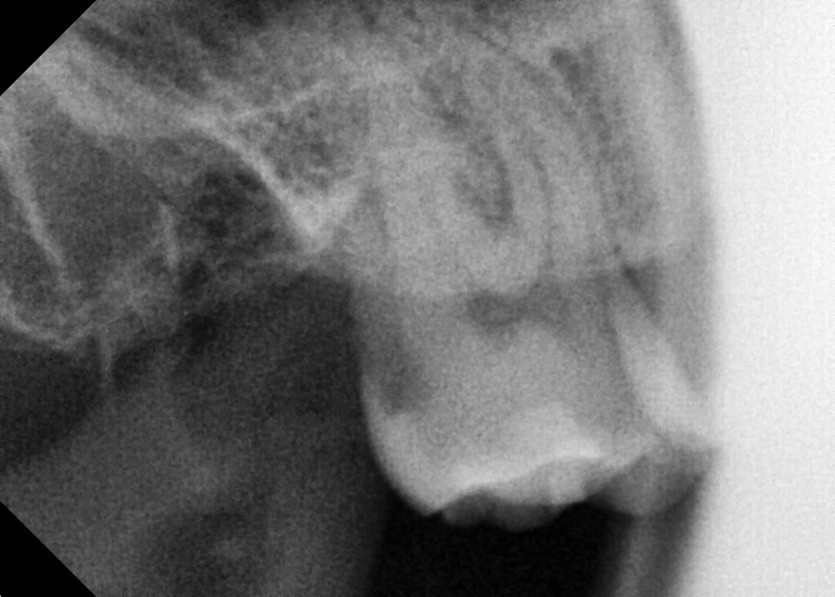

#18 사랑니 발치

구강 외과 전문의가 당일 발치했습니다.